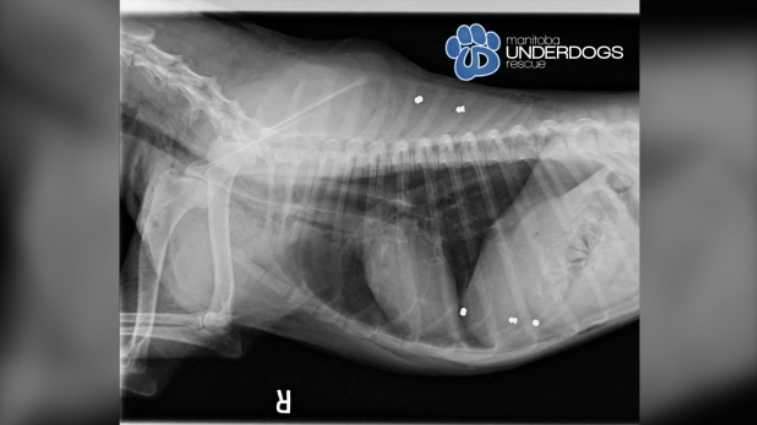

犬只救助机构Manitoba Underdogs Rescue表示,当时这条名为Greta的雌性狗,身上还有被其他狗咬伤的痕迹,被紧急送往宠物医院救治,结果发现还存在金属中毒问题,通过X光扫描,在牠身上发现6处被弹丸枪打中的痕迹,并在胃部留有大块金属。

光片显示受害狗体内有6颗子弹 CTV图